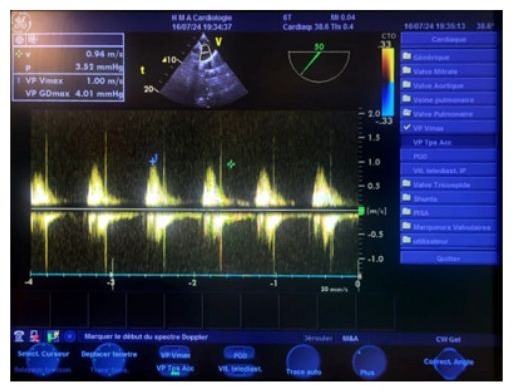

Figure 19: Transesophageal echocardiography (TOE) at the upper esophageal level, at a 50° oblique plane, with continuous Doppler pointed a few millimeters below the pulmonary valve, showing a maximum average velocity of 0.95 m/s, an average velocity of 0.56 m/s, a maximum mean gradient of 4 mmHg, an isovolumic time (IVT) of 20 cm, and the absence of any detectable pulmonary.